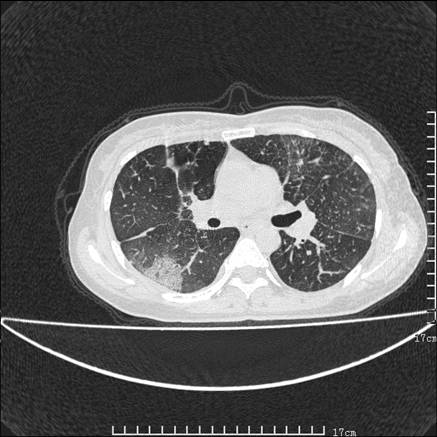

女,46岁,患胃溃疡多年,溃疡大小约1.0cm左右,后于5年前手术,病理为胃癌。主诉:半月前感冒后胸闷,气短,有咳嗽,无明显咳痰,无发热。偶有腰背部不适。

以下为高分辨扫描图像

双肺小叶间增厚,双肺散布粟米影和磨玻璃状影,以双肺上叶为重。结合病史考虑转移(癌性淋巴细管炎)可能性大。

结合病史:认为是典型肺部癌性淋巴管炎、淋巴结转移。请看图解。

正如caihe主任所言,影像表现结合临床病史应该支持肺癌性淋巴管炎;上肺大片边缘不清的渗出病变,多系感染所致,临床有感冒病史并咳嗽表现。肺癌性淋巴管炎临床一般无咳嗽、咳痰症状。

肺癌性淋巴管炎征象分为主要征象及合并征象,主要征象包括:

1、近肺门支气管血管周围间质结节状增厚;

2、小叶间隔结节状增厚;

3、小叶中央间质结节状增厚;

4、胸膜下间质结节状增厚。

合并征象为:纵隔淋巴结增大,胸腔积液,肺多发随机分布的小结节等。